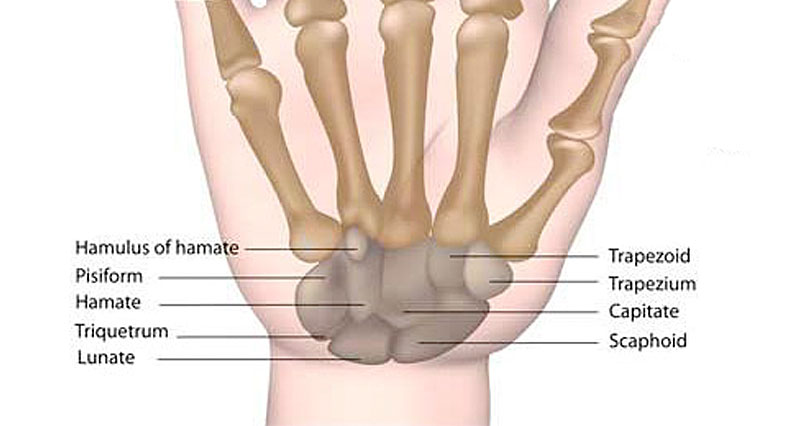

Anatomy of Wrist

Image taken from sportsinjuryclinic.net

Appearance of Wrist in Axial CT Image